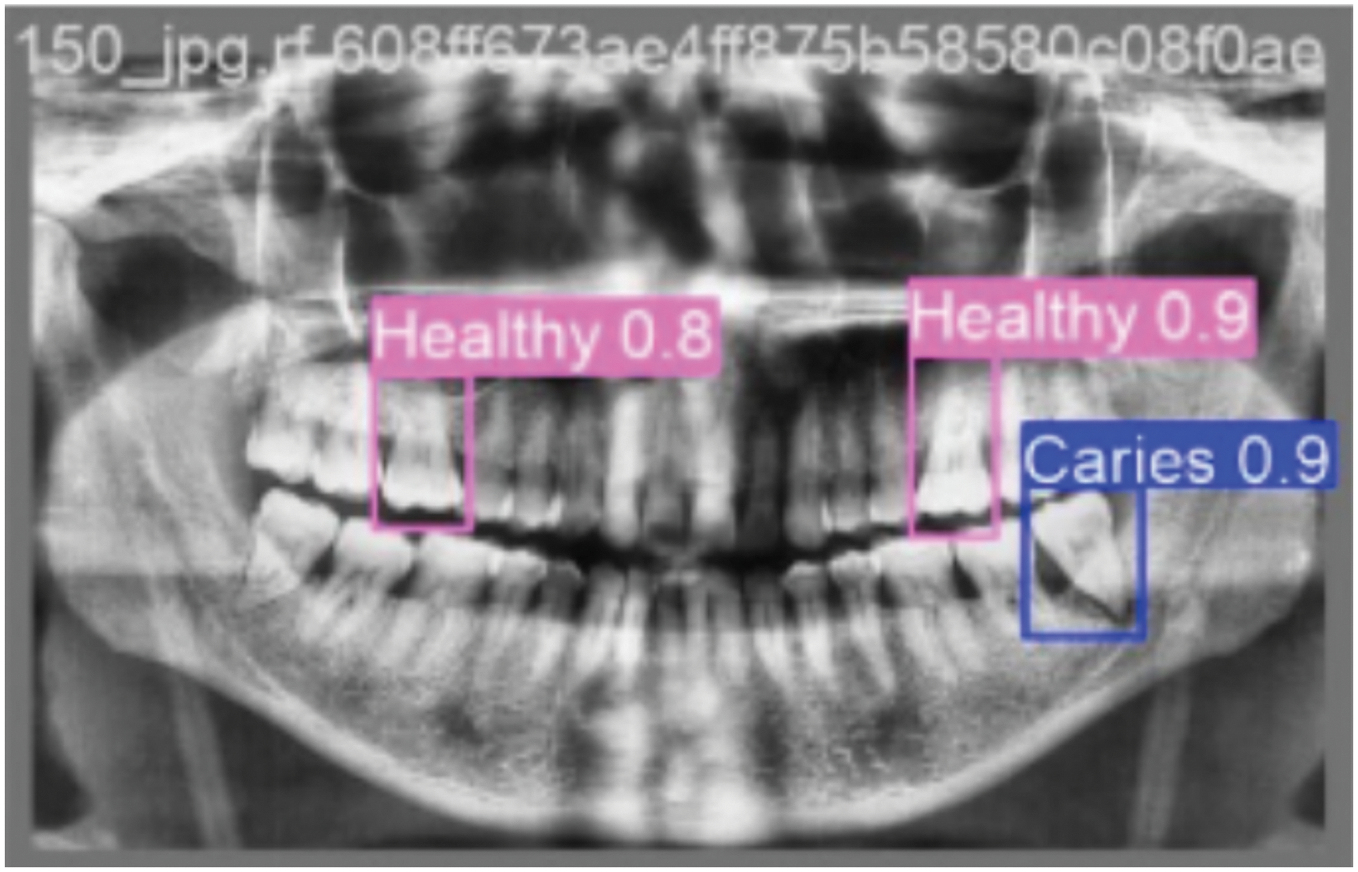

Upon processing an input OPG image during inference, the trained YOLOv5m model generates several key outputs for each detected dental pathology: Bounding Boxes: Coordinates defining a rectangular region, localizing the detected pathology. Class Labels: The predicted type of dental condition for each bounding box (e.g., Caries, Infection, Impacted Teeth, Fractured Teeth, Broken Crown, or Healthy). Confidence Scores: A numerical value (typically between 0 and 1) associated with each detection, indicating the model’s confidence in the presence and classification of the pathology within the predicted bounding box. These outputs can be visualized by overlaying the bounding boxes and labels on the original OPG image or can be provided in a structured format (e.g., JSON) for further analysis or integration into other systems. Post-processing steps like Non-Maximum Suppression (NMS) are applied to refine these raw detections by eliminating redundant or overlapping boxes for the same object instance. The final output typically consists of the original OPG image overlaid with the predicted bounding boxes for each detected pathology. The class label (e.g., “Healthy ”, “Caries”) and the confidence score associated with each bounding box as shown in Fig. 6.

Figure 6: Shows the annotated bounding boxes highlighting different dental conditions

The trained YOLOv5m model demonstrated efficient processing on the Tesla T4 GPU, with an average total time of approximately 28.3 ms per OPG image (2.6 ms preprocess, 24.9 ms inference, 0.8 ms post-processing/NMS). This corresponds to a throughput of roughly 35 frames per second, underscoring its potential for timely clinical application.